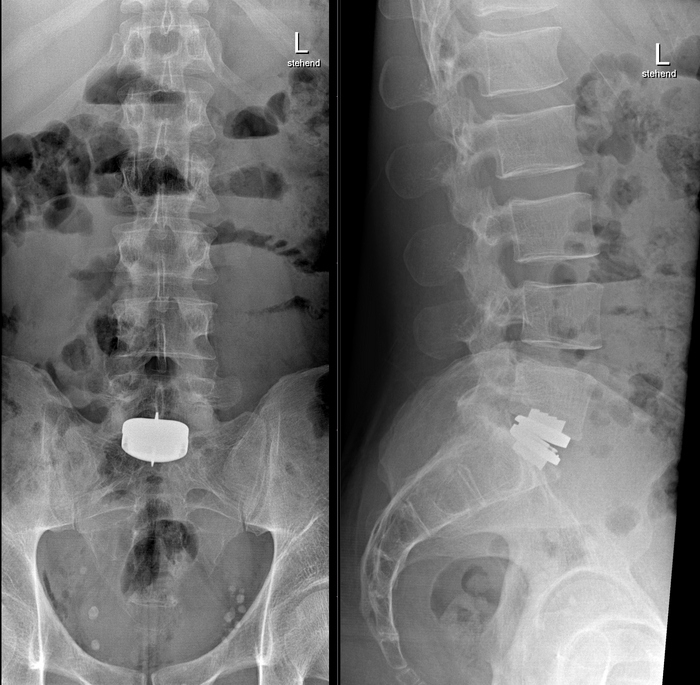

Ну и под конец перейдём к позвоночнику, где протезируют:

- межпозвоночные диски

- тела позвонков

1/3